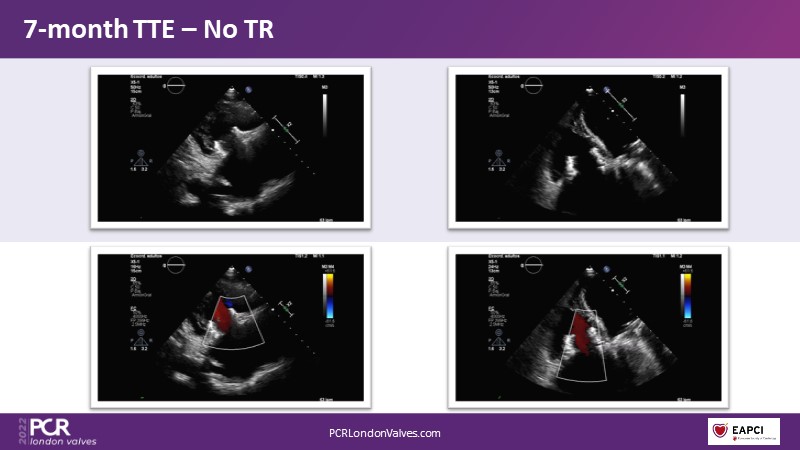

In this session from PCR London Valves 2022, discover the new Venus MedTech technology for tricuspid and pulmonary valve replacement, and a review of the clinical indications, selection criteria and procedural details.

- To learn more about the clinical experience and outcomes with Cardiovalve tricuspid and Venus P-valve